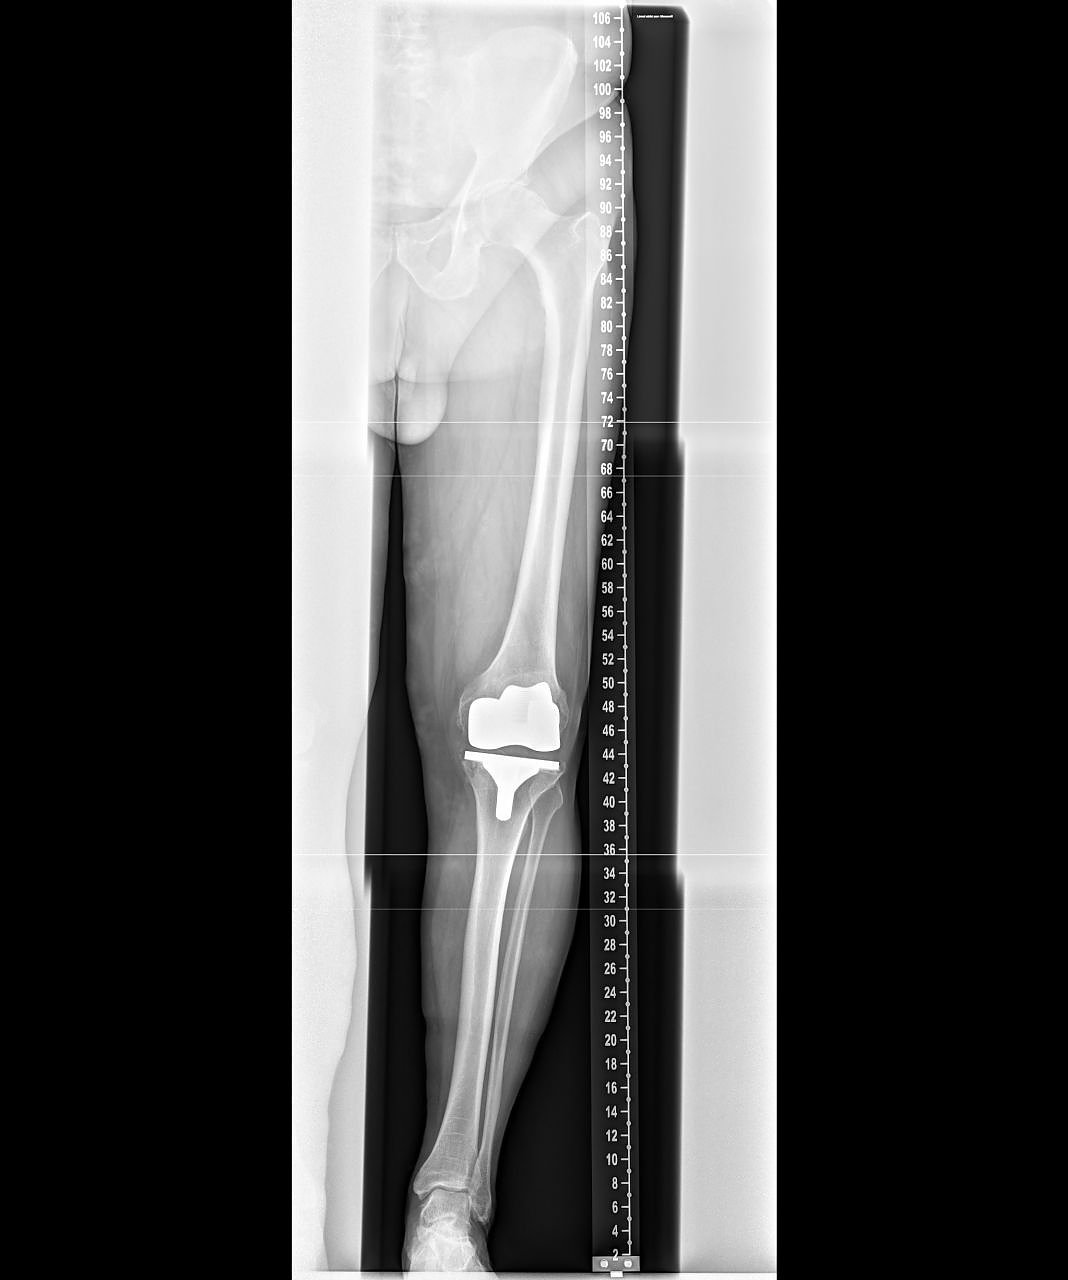

Außerdem ermöglicht die neue Röntgeneinheit die Anfertigung von Ganzbein- und Ganzwirbelsäulenaufnahmen direkt digital mit nachfolgender elektronischer fehlerfreier und versatzfreier Zusammenfügung der Bilddatensätze. Diese Ganzbein- und Ganzwirbelsäulenaufnahmen sind für die Planung endoprothetischer Versorgungen wesentlich. Darüber hinaus sind sie von großem Nutzen in der Therapieabschätzung bei Skoliose oder anderer Fehlstellungen der Wirbelsäule. Auch bezüglich der Bildqualität von im Liegen anzufertigenden Aufnahmen bietet das System wesentliche Vorteile. Häufig werden heutzutage Liegendröntgenaufnahmen mit Verwendung eines Rasters durchgeführt, um die sonst bildqualitativ beeinträchtigende Streustrahlung zu verringern. Die Röntgendosis steigt aber durch diese Rastertechnologie. Alternativ muss man die sonst schlechtere Bildqualität bei Liegendaufnahmen in Kauf nehmen, was die Befundung beeinflussen kann. Nach unserer Kenntnis erstmalig in Thüringen verfügbar, ist nun für diese schwerkranken Patienten (die deshalb nur im Liegen geröntgt werden können) das sogenannte Sky Flow Processing”, erklärt der Chefarzt.